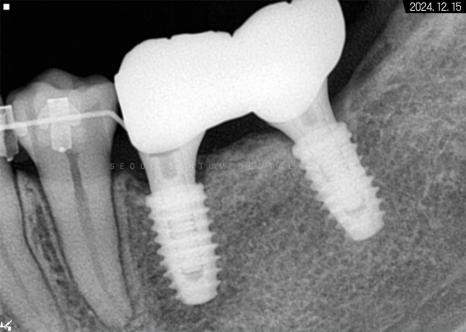

따라서 적정 시기에

CT를 촬영해 치조골 폭과 밀도를

철저하게 분석한 다음 정확한 자리를 선정하고

임플란트 식립을 진행했습니다.

하악 좌측 사랑니 발거 후

임플란트가 필요한 부분들에

픽스처를 견고하게 식립해 드렸습니다.

일정 기간이 지난 후 고정력을 체크하고

지대주에 이어서

크라운까지 예쁘게 수복해 드렸습니다~

크라운으로 감싸고 난 후의 치근단 모습입니다.

정확한 간격으로 견고하게 심어졌으며

주변 치조골 양도 풍부합니다.